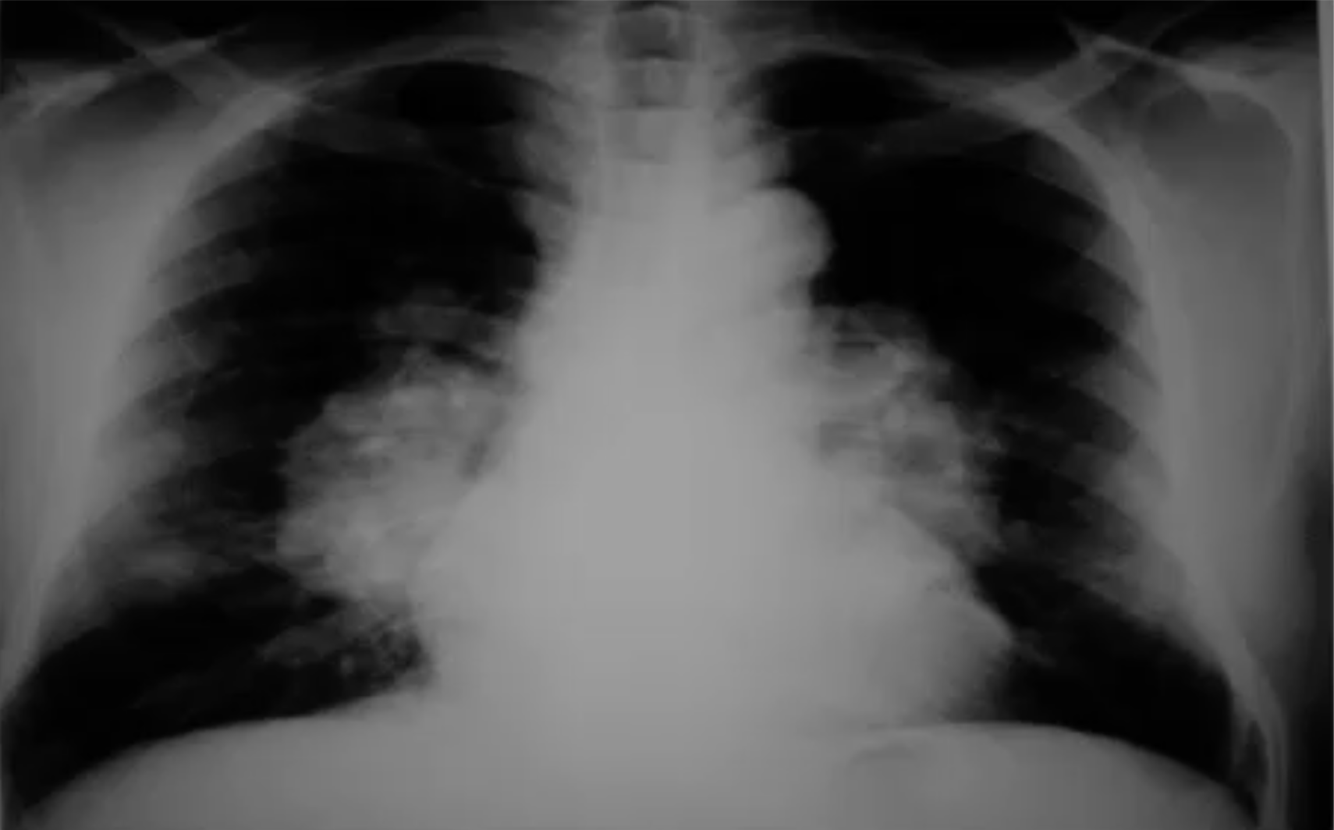

What does this CXR show?

Cardiomegaly/Pericardial Effusion

Heart size > 50% of the lung fields.